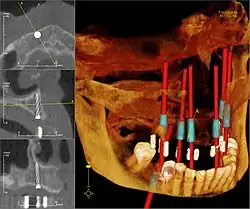

Wichtigster Bestandteil von CAS ist die Entwicklung eines präzisen Modells des Patienten. Dies kann durch bildgebende Verfahren wie Computertomographie, Magnetresonanztomographie, oder Ultraschall geschehen. Die Aufnahmen werden heute in der Regel schon digital erstellt und müssen nicht mehr eingescannt werden. Es ist sinnvoll, mehrere Modalitäten zu kombinieren. Beispielsweise sind MR-Bilder sehr kontrastreich, aber nicht geometrisch genau; CT-Daten sind dagegen strecken- und winkeltreu im Rahmen der Auflösung des verwendeten Scanners. Die Bilder können parallel nebeneinander präsentiert oder optisch überlagert werden (Datenfusion). Die Fusion kann halb- oder vollautomatisch erfolgen. Ziel ist ein 3D-Datasets, der die exakte räumliche Lage der normalen und krankhaft veränderten Gewebe und Strukturen der Zielregion wiedergibt. Die Bildanalyse schließt die Bearbeitung des 3D-Modells des Patienten ein, um die relevanten Informationen zu extrahieren. Durch die unterschiedlichen Kontraststufen der verschiedenen Gewebe kann zum Beispiel ein Modell so geändert werden, dass nur feste Strukturen wie Knochen gezeigt werden, oder aber der Verlauf der Arterien und Venen durch das Gehirn sichtbar ist.

Ein Datensatz kann zum Beispiel Daten von 180 CT-Schichten enthalten, 1 mm dicke Schichten in 1 mm Abstand mit jeweils 512 × 512 Pixel. Die Details sowohl der weichen als auch der festen Gewebestrukturen können automatisch segmentiert und dann optisch getrennt dargestellt, z. B. farblich markiert oder dreidimensional freigestellt werden. Von Hand werden Orientierungspunkte („land marks“) gesetzt, um in der Lage zu sein, zu einem späteren Zeitpunkt den virtuellen Datensatz neu auszurichten und mit der Situation während der Operation abzugleichen (Bildregistrierung).

Professionelle medizinische Betrachtungssoftware (DICOM-Viewer, z. B. OsiriX) kann den segmentierten und markierten Datensatz des Patienten als virtuelles 3D-Modell wiedergeben. Dieses Modell kann rotiert, beschnitten und gefiltert werden, um dem Chirurgen Ansichten aus jedem möglichen Blickwinkel und jeder Tiefe zu liefern. So kann der Chirurg den Fall besser beurteilen und eine genauere Diagnose stellen. Dann wird die chirurgische Intervention geplant und virtuell simuliert, bevor die eigentliche Operation stattfindet. Steht ein Operationsroboter zur Verfügung, wird er nun programmiert, die geplanten Aktionen während des aktuellen chirurgischen Eingriffs durchzuführen.

Wichtigstes Einsatzgebiet der CAS ist die Neurochirurgie am Gehirn. Remote Manipulatoren werden dafür schon seit den 1980er Jahren genutzt. In der Kieferchirurgie ist Knochensegmentnavigation ein modernes Konzept bei Operationen am Kiefergelenk oder bei der Gesichtsrekonstruktion.[1] Die navigierte Implantologie ist ein prothetisch-chirurgisches Hilfsverfahren in der Mund-Kiefer- und Gesichtschirurgie und der Zahnmedizin, um Zahnimplantaten exakt in den Kieferknochen einzusetzen. HNO-Chirurgen kennen ebenfalls Gebiete mit eingeschränktem Zugang und der Notwendigkeit hochpräzisen Handelns wie zum Beispiel bei der Mittelohr-Chirurgie.[2] Die Computerassistierte orthopädische Chirurgie (CAOS) ist in der Orthopädie weit verbreitet, vor allem im Hüft-[3] und Kniegelenkersatz.[4] Sie ist außerdem nützlich zur Operationsplanung und -führung in der Osteosynthese von verschobenen Knochenbrüchen. In der allgemeinen und gynäkologischen Chirurgie sind Bauchspiegelungen Nutznießer dieses Fortschritts, etwa für die Hysterektomie (Gebärmutterentfernung). In Montreal wurden 1994 mit Mikromanipulatoren Gallenwegsoperationen computergesteuert durchgeführt.[5] In der Herzchirurgie können Steuerungssysteme den Mitralklappenersatz oder die Ventrikularstimulation über kleine Thorakotomien durchführen. In der Urologie helfen chirurgische Roboter bei der Pyeloplastik (Nierenbeckenplastik), bei der Nephrektomie (operative Entfernung einer Niere), und bei Eingriffen an der Prostata.[6][7]